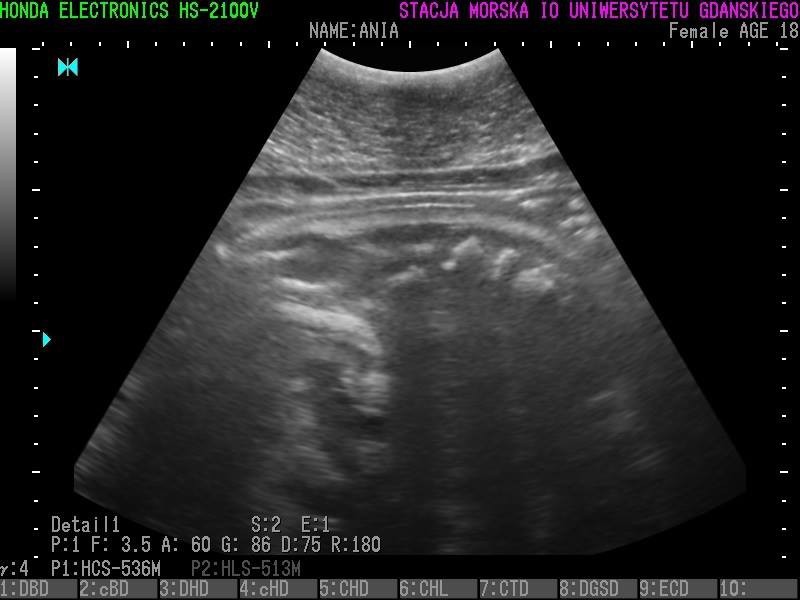

Wszystkie helskie foki - czyli Agata, Ewa, Unda Marina i Ania - są w ciąży. To wyniki badań ultrasonograficznych, które przeprowadzono w miniony piątek (23 grudnia).

• Z radością więc informujemy, że tego roku wszystkie nasze cztery samice spodziewają się potomstwa - czytamy na profilu Fokarium.

Szczenięta urodzą się najprawdopodobniej w marcu 2017 roku.